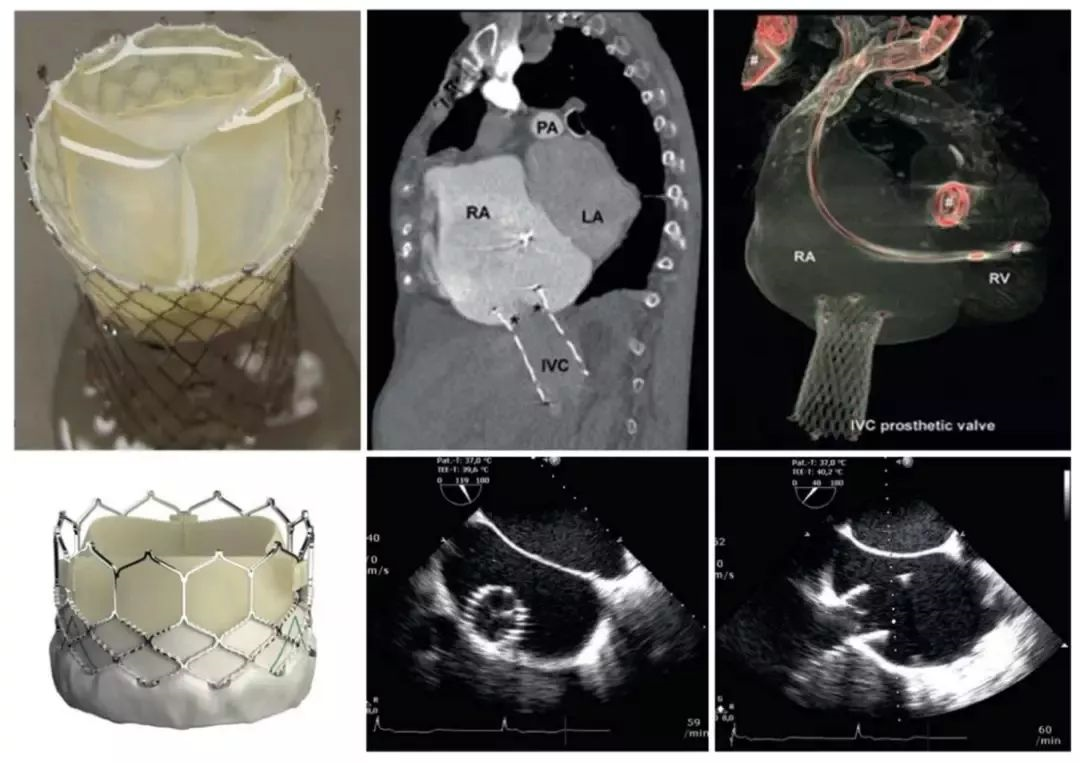

4. 三尖瓣膜置换

经导管三尖瓣置换是治疗三尖瓣反流的根本解决方法。NaviGate 生物瓣膜是目前唯一批准可用于自身三尖瓣的介入瓣膜,由房室瓣支架和一个输送系统组成。瓣膜由镍钛合金锥形支架及3片异种心包瓣叶组成。支架周边为多个短边及环形小翼,以确保瓣膜支架牢固锚定于三尖瓣环己三尖瓣叶上。

另外经导管Sapien瓣膜通过股静脉植入三尖瓣,但缺乏明确的瓣膜放置点。Melody肺动脉瓣是一种牛颈静脉瓣,有研究者通过将经皮Melody肺动脉瓣假体植入右心房来治疗三尖瓣反流,但是此手术需要退化的生物假体,提供用于固定的基础。

图10: 经导管三尖瓣置换技术